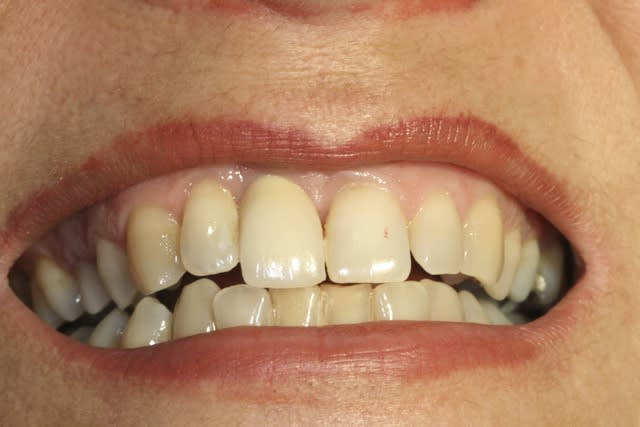

Ci joint cas avec membrane résorbable laissée exposée volontairement ( technique Bio coll proposée par Anthony G. Scar dans les années 2000 remis au gout du jour par tarnow en 2006 ).

Celà ne marche pas avec toutes les membranes...

fig 1 coupe tomo Jo

fig 2 vue clinique ( léger décalage des collets entre 11 et 21 )

fig 3 exo

fig 4 pose membrane résorbable + os xénogène

fig 5 membrane suturée

fig 6 réouverture J0 + 6mois

fig 7 vue clinique J0 + 2ans ( Prothèse Dr G.D 31 )

fig 8 vue clinique JO + 5ans (léger décalage des collets entre 11 et 21 comme à l'origine)

fig 9 radio J0 + 5 ans

En tant que "voyeur", voilà en PJ ce que vous êtes susceptible de voir chez cette Dame.

fig1 avant

fig2 aprés.